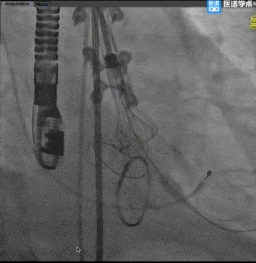

主动脉根部造影

球囊预扩

TaurusElite®顺利过弓

TaurusElite®首次释放